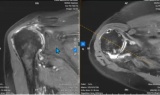

Giải pháp điều trị bệnh lý cơ xương khớp công nghệ cao tại bệnh viện thuộc top 10 tốt nhất thế giới -